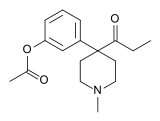

The pharmacodynamic response to an opioid depends upon the receptor to which it binds, its affinity for that receptor, and whether the opioid is an agonist or an antagonist. For example, the supraspinal analgesic properties of the opioid agonist morphine are mediated by activation of the μ1 receptor; respiratory depression and physical dependence by the μ2 receptor; and sedation and spinal analgesia by the κ receptor. Each group of opioid receptors elicits a distinct set of neurological responses, with the receptor subtypes (such as μ1 and μ2 for example) providing even more [measurably] specific responses. Unique to each opioid is its distinct binding affinity to the various classes of opioid receptors (e.g. the μ, κ, and δ opioid receptors are activated at different magnitudes according to the specific receptor binding affinities of the opioid). For example, the opiate alkaloid morphine exhibits high-affinity binding to the μ-opioid receptor, while ketazocine exhibits high affinity to ĸ receptors. It is this combinatorial mechanism that allows for such a wide class of opioids and molecular designs to exist, each with its own unique effect profile. Their individual molecular structure is also responsible for their different duration of action, whereby metabolic breakdown (such as N-dealkylation) is responsible for opioid metabolism.

Phenylpiperidines

- Pethidine (meperidine)

- Ketobemidone

- MPPP

- Allylprodine

- Prodine

- PEPAP

- Promedol